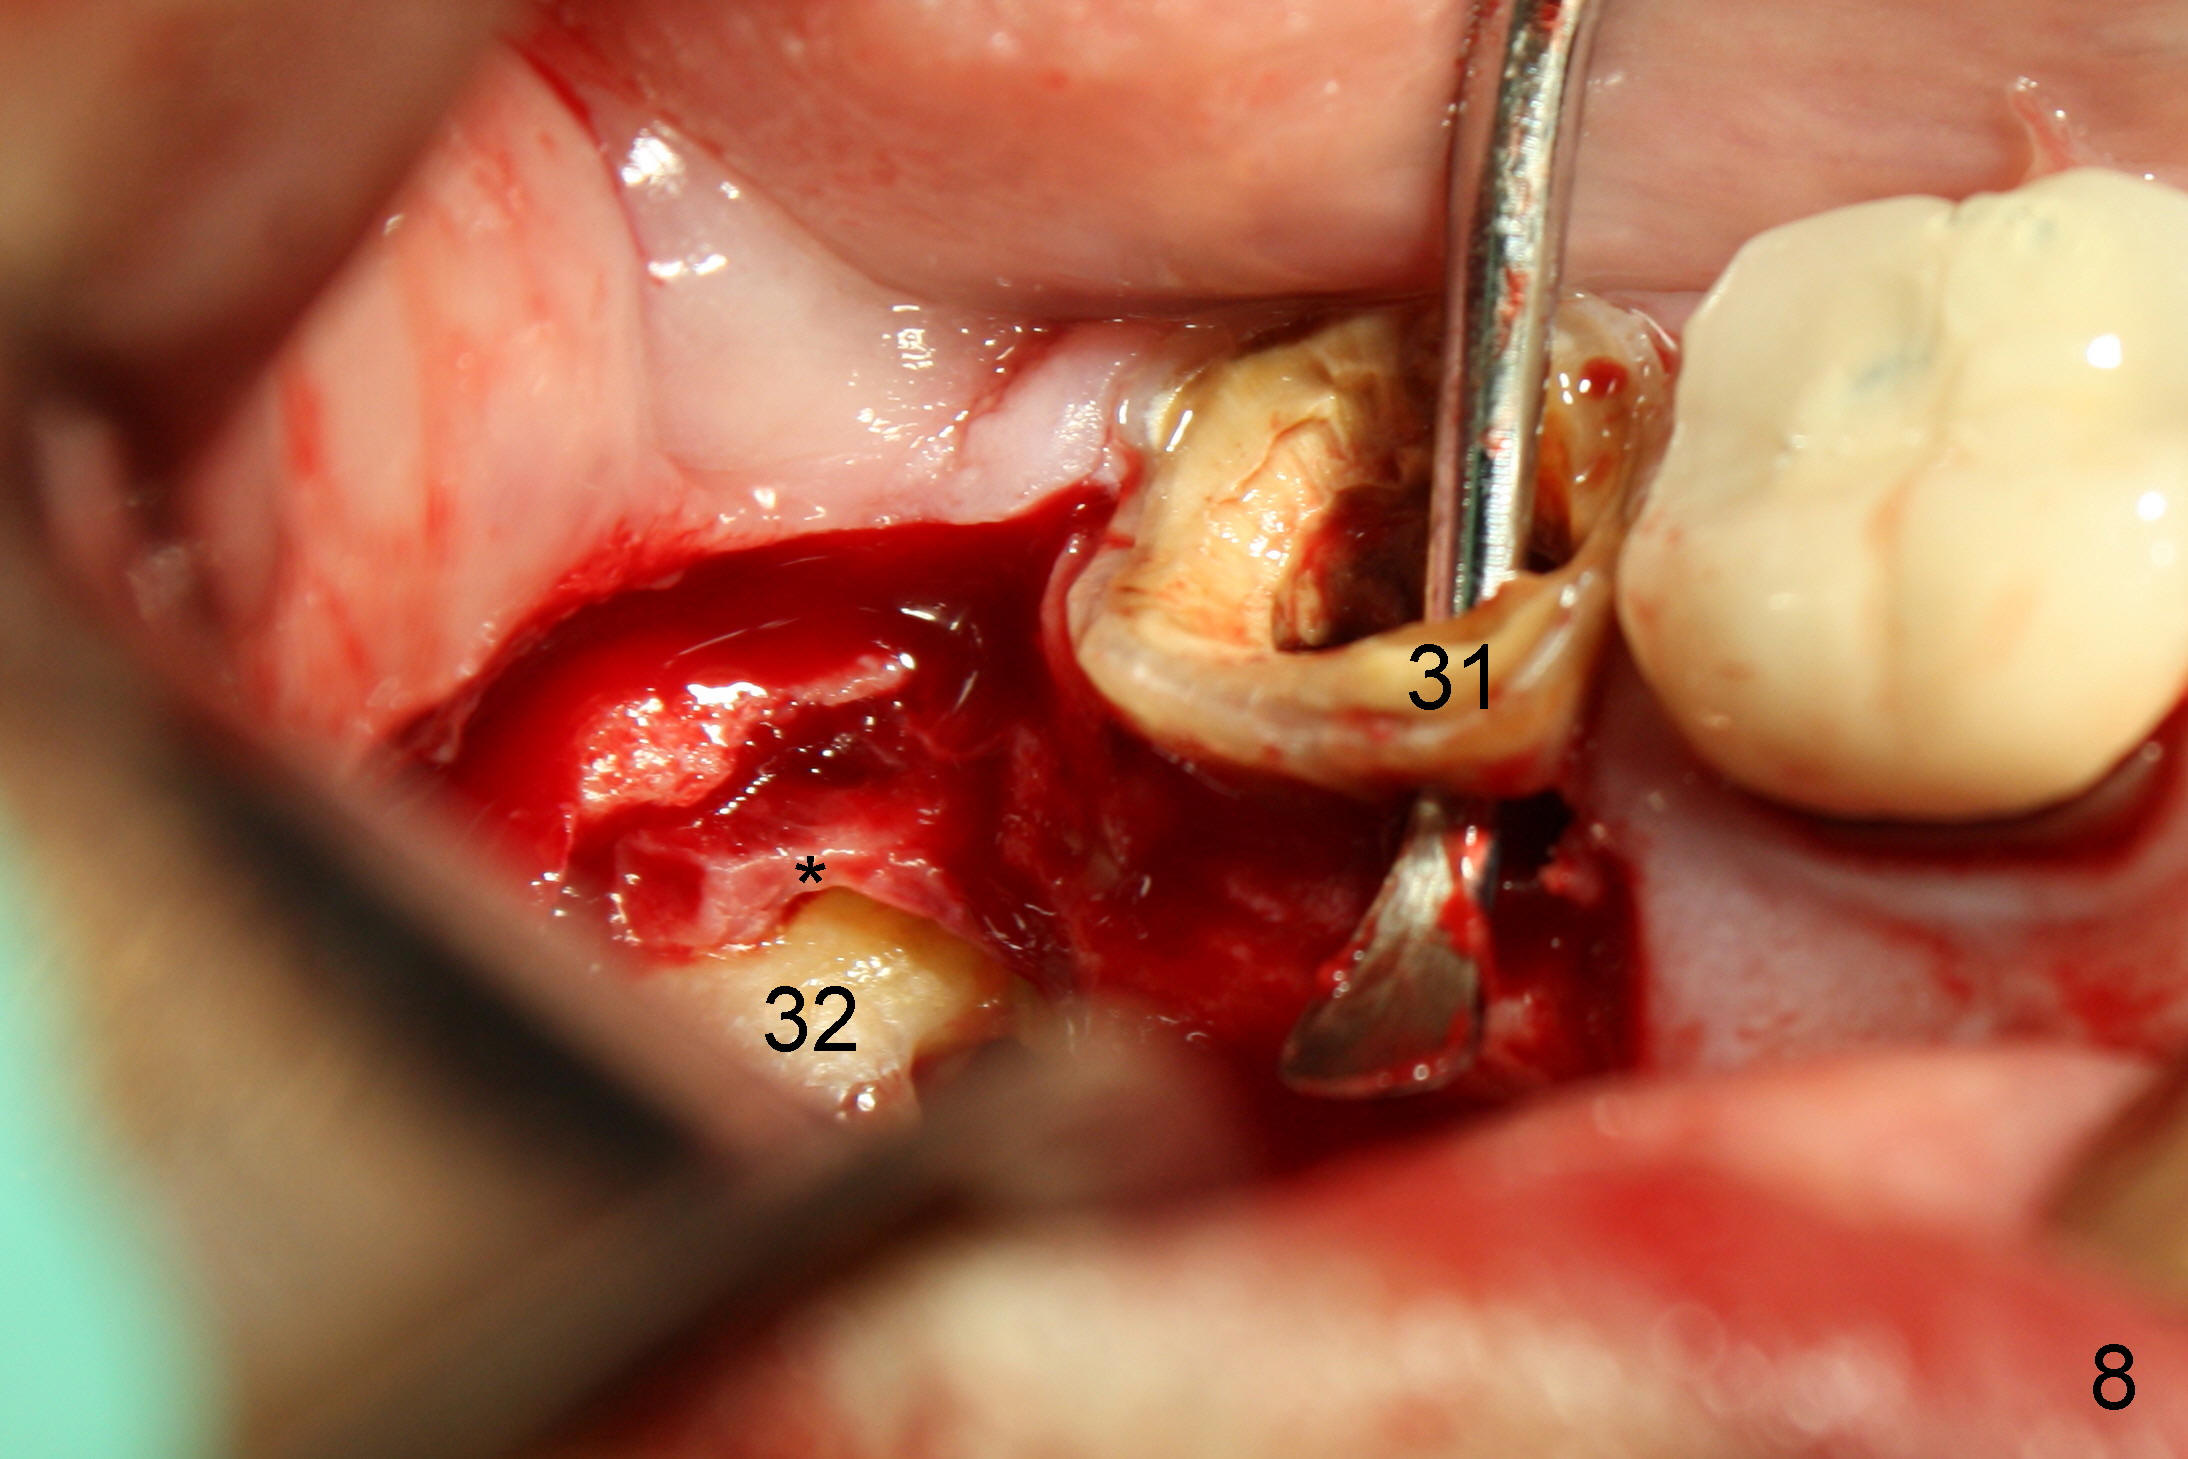

#32 (Fig.6). The latter is sectioned for easy removal (Fig.7 arrowhead);

there is yellowish exudate from the cyst (*). Nonsalvageability of #31 is

confirmed (Fig.8). Extraction of #31 shows the septum (Fig.9).